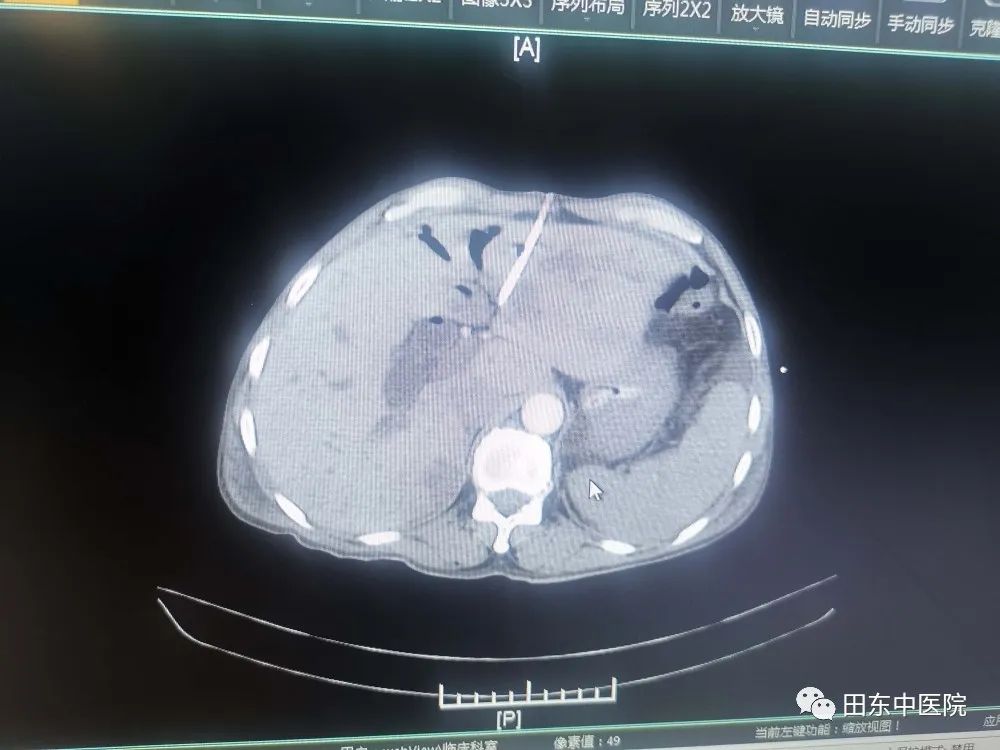

患者入院时有腹部剧痛、黄疸、寒战高热等症状,通过腹部CT增强、磁共振增强+胆道水成像等检查后,发现患者有:1、急性梗阻性化脓性胆管炎 2、脓毒血症 3、感染性休克 4、梗阻性黄疸 5、腹膜炎等多项急危重症,病情岌岌危重,急诊行PTCD引流术,经积极抗感染、扩容、抗休克、护肝退黄等措施把患者从死亡边缘抢救过来。